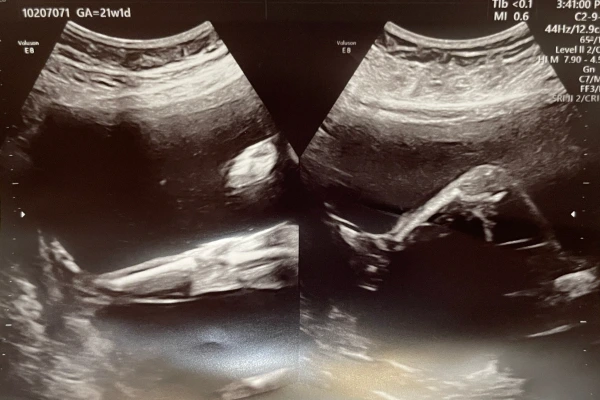

24.08.07 누굴 닮았나~ (21주1일)

작디작은 새싹이에서 이제는 눈코입도 다 보이고, 꼬물꼬물 거리던 팔다리도 모양을 갖춰가네.

평소에 그렇게 엄마 배를 뻥뻥 차대던 건강이 다리가 저런 모습이었구나.